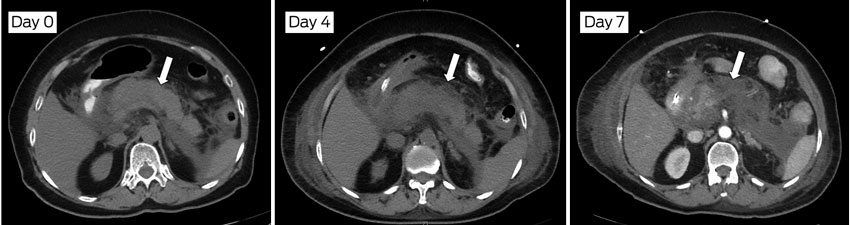

Routine use of CT scanning is not recommended in patients with a clear diagnosis of pancreatitis established by the presence of the first two criteria. CT scanning should be reserved for those whose condition fails to improve clinically after 5 days to assess the severity and extent of necrosis, as it is after this time interval that the presence and extent of pancreatic necrosis are most obvious (Box 2).9,10 The reason for not performing routine early CT scans is based on strong evidence that they do not improve clinical outcomes, increase the risk of contrast allergy and nephrotoxicity, and increase the duration of hospital stay.15,16